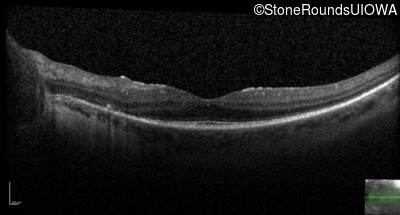

Optical Coherence Tomography - Right - 20/32

Exemplar / OCT Stack